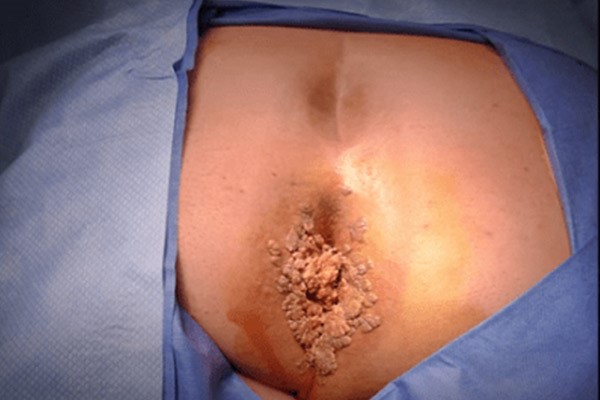

Anal wart or condyloma acuminata is a benign skin lesion that occurs in or around the anus and is caused by infection with the human papilloma virus.HPV virus) is These warts are usually asymptomatic and therefore known as “silent disease of the anus”. Many people may ignore warts until they grow the news be and realize their existence only by touch or examination.

Symptoms of anal warts in women

Anal warts in women usually appear as small, soft bumps in or around the anus and may be colored. coffee They should be pink or blue. Also, their shape can be similar to cauliflower. Women may feel itching, burning or discomfort in these areas, which becomes annoying when sitting or doing daily activities.